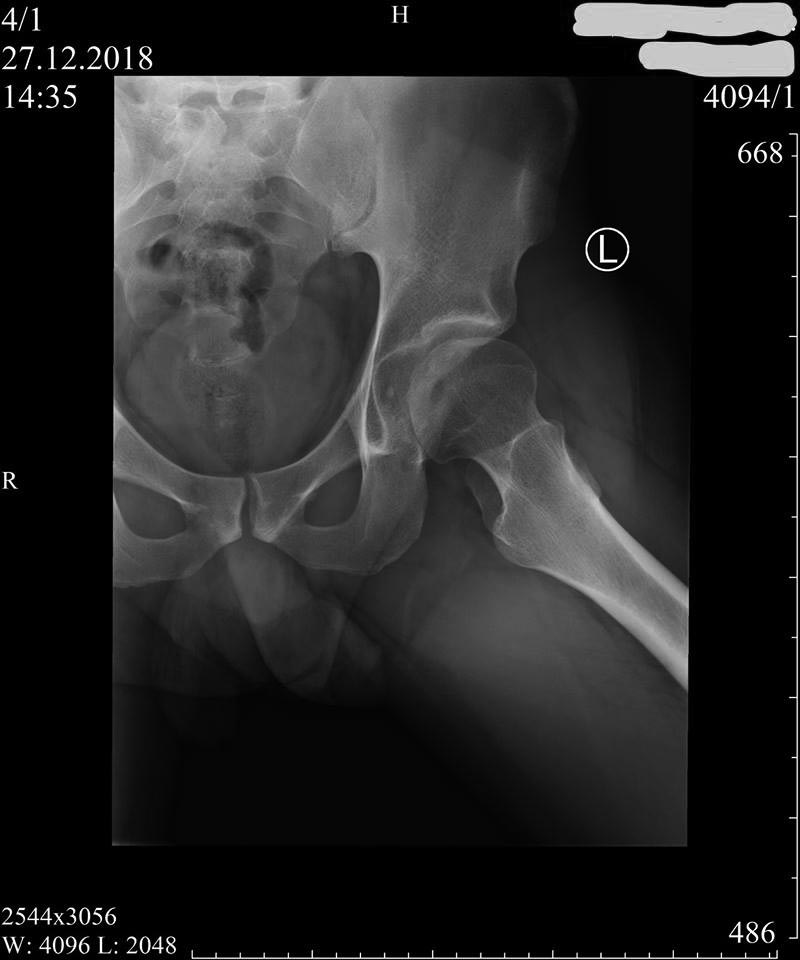

Пациент 27 лет: с 14-ти - "щёлканье" в тазобедренных суставах...

Последние полгода - боль (особенно после вставания из положения сидя),

которая устраняется "встряхиванием" ноги (правой) со "щелчком"...

Владимир Георгиевич Босых (профессор МГМСУ) полагает, что на

рентгенограммах: "ярко выраженный подвывих бедра и в зависимости от

клиники надо ставить вопрос о хирургической коррекции (возможно, тройной

остеотомии таза)".